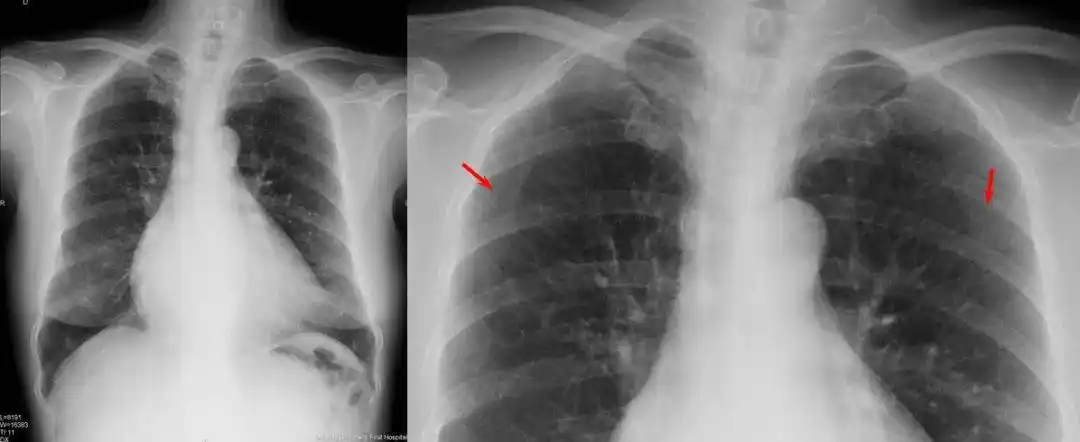

高清!心血管疾病最全影像图解